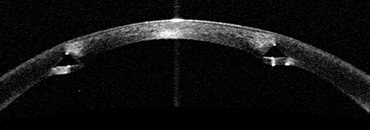

케라링 삽입 후 전안부OCT 2012년.

양훈 원장 제공